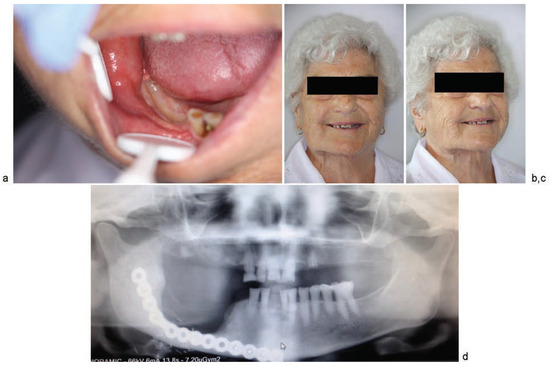

Clinical Cases